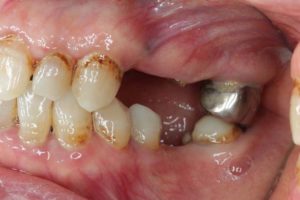

院長のコメント

長い間お疲れ様でした。この患者さんは、奥歯を何本も失っていて満足なお食事ができない状態でした。前歯も所々虫歯で黒ずんでいて気になって口を開けて笑えないとおっしゃっていました。そもそも、最初はお嬢様の結婚の前までに綺麗にしたいというものだったのですが、治療をしていくうちに奥歯の大切さを実感していただいたようです。

さて、この方は奥歯にインプラントを入れたのですが、あまり骨がなく普通の手術ではインプラント入れらません。そのため、インプラント手術だけならほとんど痛みはないのですが、上顎洞挙上術という難易度の高い手術を併用したため、手術後に痛みや腫れが若干出たようです。

奥歯にインプラントを入れ、前歯はホワイトニングやダイレクトボンディング、セラミックなどで修復しました。